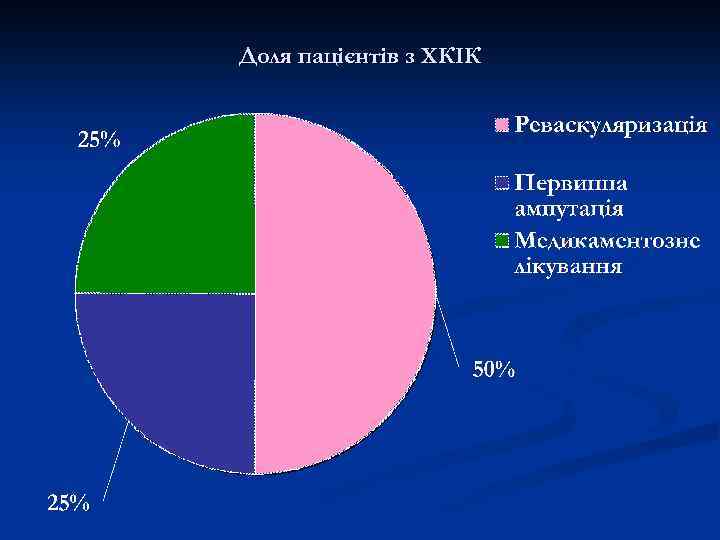

Доля пацієнтів з ХКІК

Доля пацієнтів з ХКІК

Через 6 місяців n n 40% - втратять кінцівку; До 20% - помруть.

Через 6 місяців n n 40% - втратять кінцівку; До 20% - помруть.